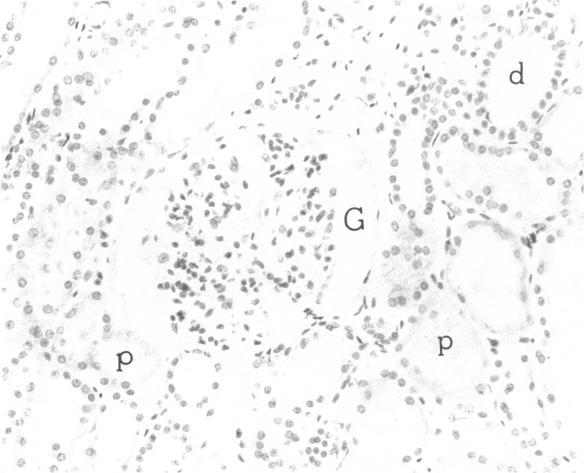

Most human pyelonephritis Escherichia coli isolates express both mannose (MS)- and globoside (Gal-Gal)-binding pili. An ascending E. coli urinary tract infection model was established in the 16-wk-old female BALB/c mouse to compare the pathogenic significance of MS and Gal-Gal pili and their efficacy as vaccines for the prevention of pyelonephritis. The distribution and density of pilus receptor compounds in urogenital tissues and as soluble compounds in urine were determined with antibodies to the synthetic receptor analogues, alpha D-Gal(1----4) beta D-Gal and alpha D-Man(1----2) alpha D-Man. Both carbohydrates were detected in vagina, bladder, ureter, and renal pelvis epithelium and in collecting duct and tubular cells. A pilus receptor compound also was detected in urine. It competitively inhibited the binding capacity of MS pili and was found to be physically, chemically, and immunologically related to Tamm-Horsfall uromucoid. Infectivity and invasiveness were quantitatively and histologically characterized for four E. coli strains: J96, a human pyelonephritis strain that expresses both MS and Gal-Gal pili; two recombinant strains prepared from J96 chromosomal DNA encoding MS pili or Gal-Gal pili; and the nonpiliated K12 recipient. Intravesicular administration of J96 (10(6) colony-forming units [CFU]) resulted in renal colonization and invasion in each of nine mice. The Gal-Gal clone (10(6) CFU) colonized the kidneys in each of 10 mice but did not invade. In contrast, the MS clone (10(6) CFU) did not colonize renal epithelium or invade. This effect was superceded when larger doses (greater than or equal to 10(10) CFU) of the MS clone were administered in volumes that cause acute vesicoureteric reflux. The efficacy was determined of vaccines composed of pure MS or Gal-Gal pili or the lipopolysaccharide containing O somatic antigen of the challenge strain, J96. The Gal-Gal pilus vaccine blocked renal colonization in 19 of 22 mice and renal invasion in 10 of 11 mice. Gal-Gal pili may be useful immunogens for the prevention of pyelonephritis in anatomically normal urinary tracts.

大多数人类肾盂肾炎大肠杆菌分离株都表达甘露糖(MS)结合菌毛和糖苷(Gal-Gal)结合菌毛。在16周龄雌性BALB/c小鼠中建立了大肠杆菌上行性尿路感染模型,以比较MS菌毛和Gal-Gal菌毛的致病意义及其作为预防肾盂肾炎疫苗的效果。用针对合成受体类似物α-D-Gal(1→4)β-D-Gal和α-D-Man(1→2)α-D-Man的抗体,测定泌尿生殖组织中菌毛受体化合物的分布和密度以及尿液中可溶性化合物的情况。在阴道、膀胱、输尿管、肾盂上皮以及集合管和肾小管细胞中均检测到这两种碳水化合物。在尿液中也检测到一种菌毛受体化合物。它能竞争性抑制MS菌毛的结合能力,并且在物理、化学和免疫学上与Tamm-Horsfall尿黏蛋白相关。对四株大肠杆菌进行了感染性和侵袭性的定量及组织学特征分析:J96,一株表达MS菌毛和Gal-Gal菌毛的人类肾盂肾炎菌株;由编码MS菌毛或Gal-Gal菌毛的J96染色体DNA制备的两株重组菌株;以及非菌毛化的K12受体菌。膀胱内接种J96(10⁶菌落形成单位[CFU])导致9只小鼠中的每只都出现肾脏定植和侵袭。Gal-Gal克隆株(10⁶CFU)使10只小鼠中的每只都出现肾脏定植,但未发生侵袭。相比之下,MS克隆株(10⁶CFU)未在肾上皮定植或侵袭。当以导致急性膀胱输尿管反流的体积给予更大剂量(大于或等于10¹⁰CFU)的MS克隆株时,这种效应被取代。测定了由纯MS菌毛或Gal-Gal菌毛或含有攻击菌株J96的O菌体抗原的脂多糖组成的疫苗的效果。Gal-Gal菌毛疫苗在22只小鼠中的19只中阻止了肾脏定植,在11只小鼠中的10只中阻止了肾脏侵袭。Gal-Gal菌毛可能是预防解剖结构正常的尿路肾盂肾炎的有用免疫原。